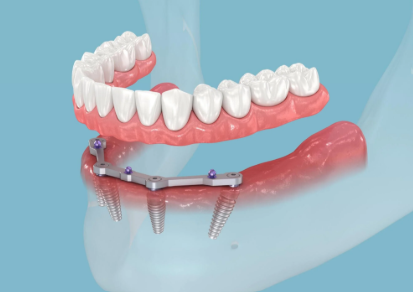

1. What Are All-on-4 Dental Implants?

4. The Step-by-Step Process of All-on-4 Implants

Here’s how the All-on-4 implant procedure works:

Step 1: Consultation and 3D Scan

Your dentist performs a thorough examination using digital X-rays and 3D scans to assess your bone condition and plan implant placement accurately.

Step 2: Implant Placement

Under local anesthesia or sedation, four titanium implants are fixed into the jawbone at specific angles for maximum stability.

Step 3: Immediate Temporary Teeth

A temporary bridge or denture is attached on the same day, so you leave the clinic with a full smile.